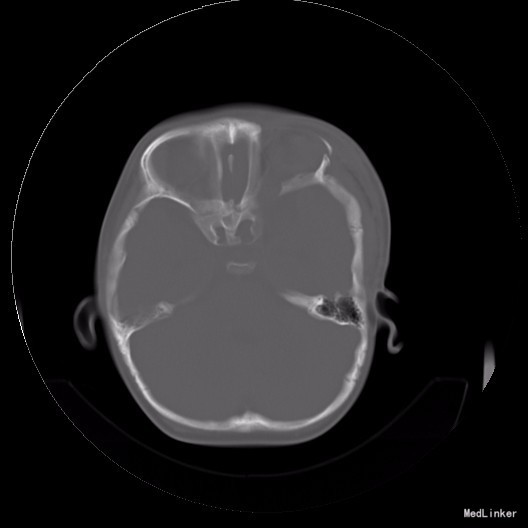

完善相关检查,在气管插管麻下行“左额眶部占位病变切除术”。术后病理诊断为“(左眼眶)丛状神经纤维瘤”。术后给予患儿脱水、营养脑神经、抗感染等对症治疗。复查CT未见明显异常。